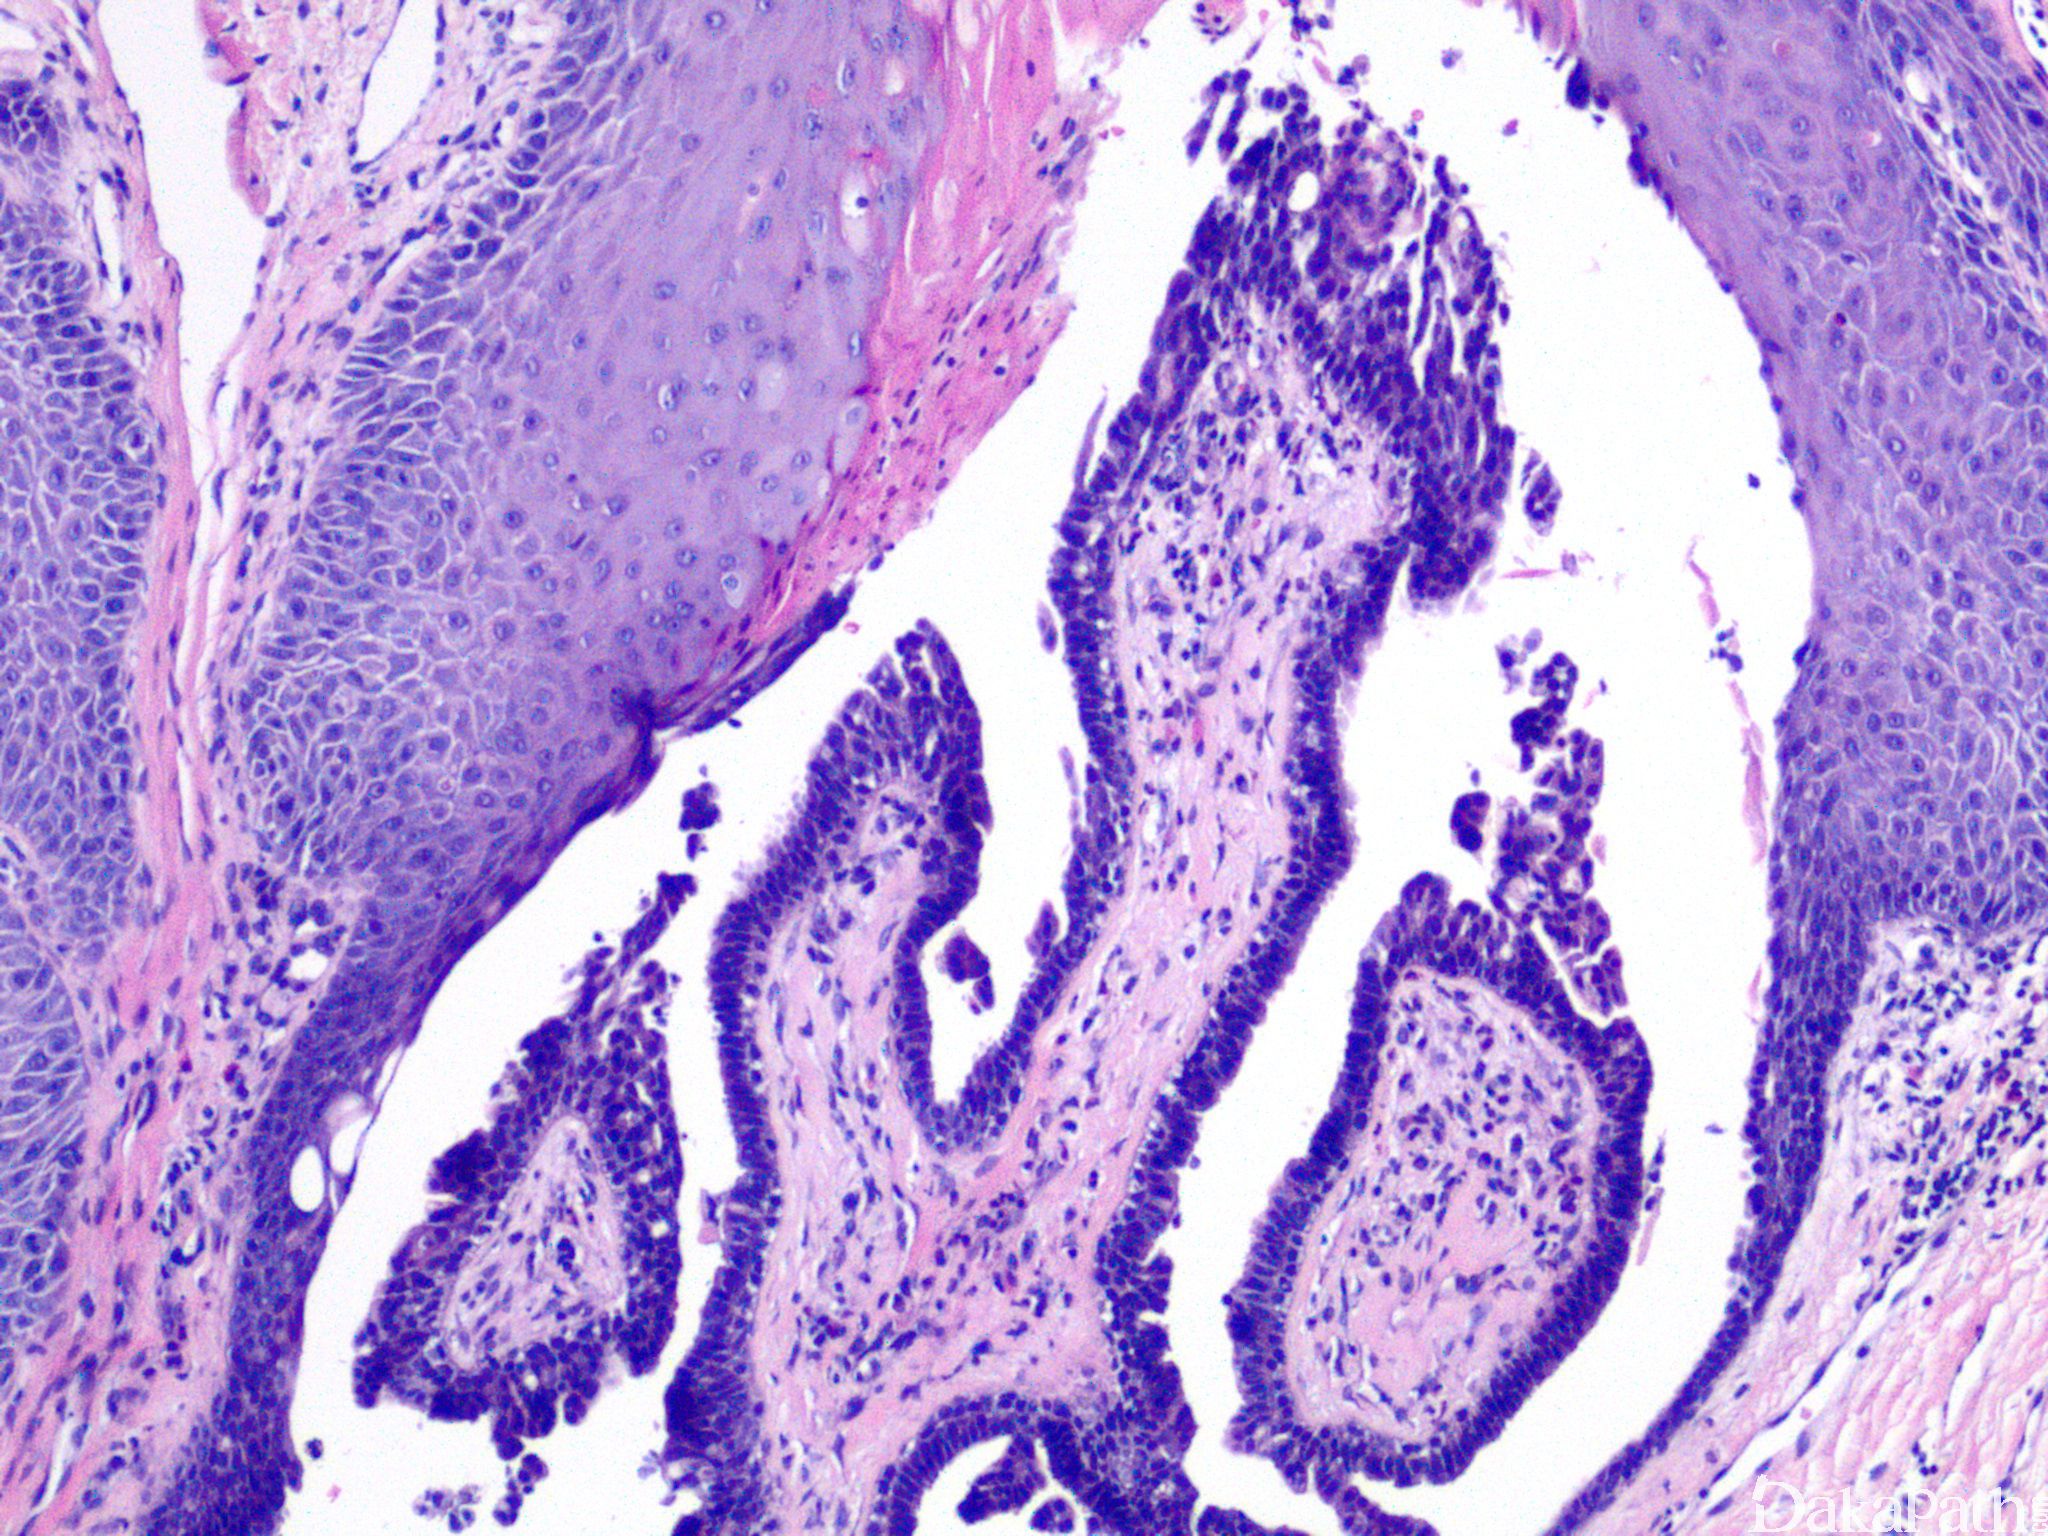

镜下见真皮内数个囊样凹陷,开口皮面,囊腔上皮与表皮鳞状上皮相连;

腺腔内可见绒毛状突起,腔壁及绒毛状突起常由二层细胞组成,内层为高柱状细胞,核卵圆形,胞浆弱嗜酸性,可见顶浆分泌,为腺上皮;外层为小立方细胞,核圆,胞浆少,为肌上皮;

间质可见大量浆细胞浸润。